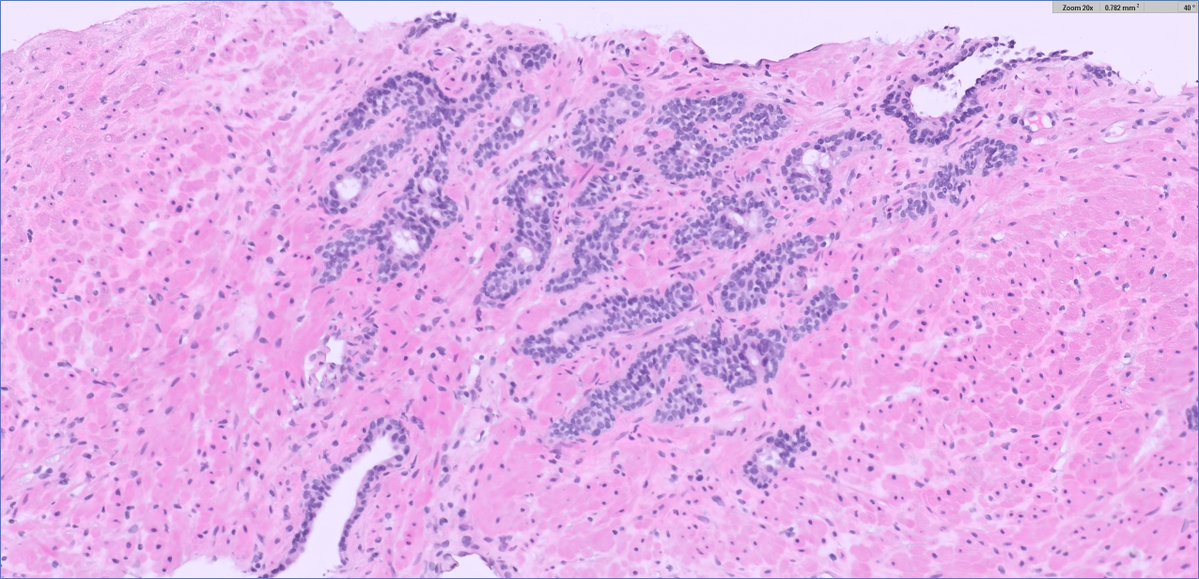

#GUpath #beautyinb9 mimic of prostate cancer on bx: 🔬basal cell hyperplasia